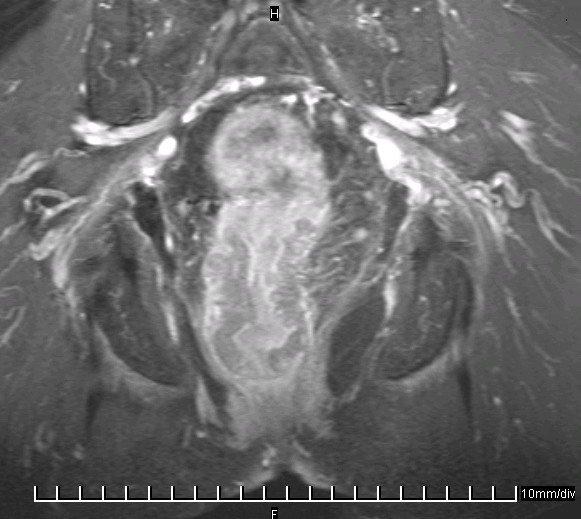

Das MRT-Bild zeigt ein distales Rektumkarzinom im Frontalschnitt. Zirkuläre Wandverdickung.![]() | |||||||||||||||||||||||||||||||||||||||||||||||||||||||